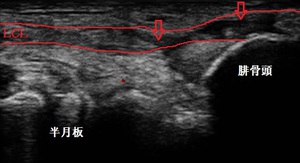

坂戸市若葉 男性 膝関節の痛み 外側側副靭帯損傷

左膝外側 超音波長軸像 右膝同部健側

坂戸市若葉 60代男性。 左膝関節の痛み、外側側副靭帯(LCL)損傷。

【原因】

スポーツジムでヨガの(牛?の)ポージング中、左膝関節に体重が掛かりながら捻ってしまいました。

瞬間的に激痛が走り、ヨガを中止しました。自宅でアイシングしましたがだんだん痛みが強く

なってきました。

当院来院時に超音波検査を行ったところ、左外側側副靭帯が損傷(部分断裂)している様子が

認められました(左上画像の矢印)。また、左膝関節内に内出血が貯留していました。

【治療】

男性は週6日、スポーツジムでランニング、ウェイトトレーニング、ヨガ、セルフ整体療法などの

プログラムを受けて汗を流しています。

左膝の痛みが解消するまでは上半身のトレーニングを可能な範囲で行ってもらいます。日常生活では

特に階段昇降が困難なので膝のサポーターで固定します。

当院では靭帯損傷を早期修復し、内出血の吸収を促進させる特殊な物理療法と疼痛と左膝関節

周囲の筋緊張緩和を目的に手技マッサージの施術を実施します。